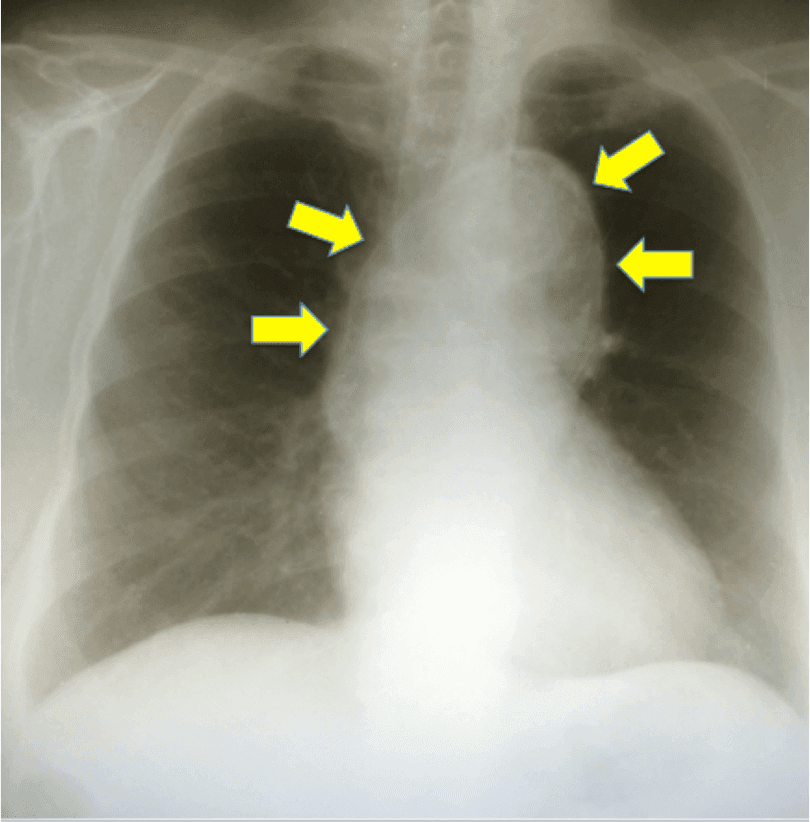

Paciente masculino, 72 anos, com queixa de dor abdominal contínua em mesogástrio há 3 dias refratária a analgésicos convencionais. No exame físico, encontra-se normal hemodinamicamente e presença de m…